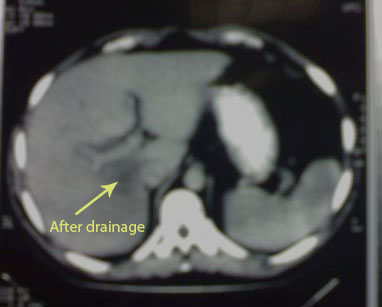

After IV umbrella of Metronidazole, (Ampicillin + Sulbactam) and (Cilastatin+Imipenem) CT guided drainage of one thousand c.c. of pus, the abscess has regressed (arrowed). Symptoms and signs subsided and general condition improved, patient discharged quite well.